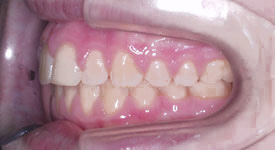

Crossbite